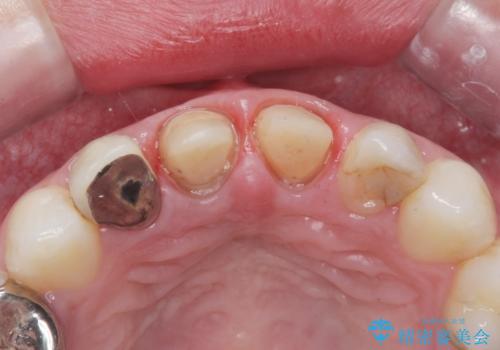

- 過去に他院で治療した前歯が取れたとの事で来院。

被せ物だけでなく中の土台まで取れていました。

歯の根っこのお掃除(根管治療(保険))を行い、土台を立ててセラミックの被せ物で治療しました。

また、隣の歯も被せ物の適合が悪く予後がよくないので根管治療(保険)を行い、セラミックの被せ物で治療を行いました。